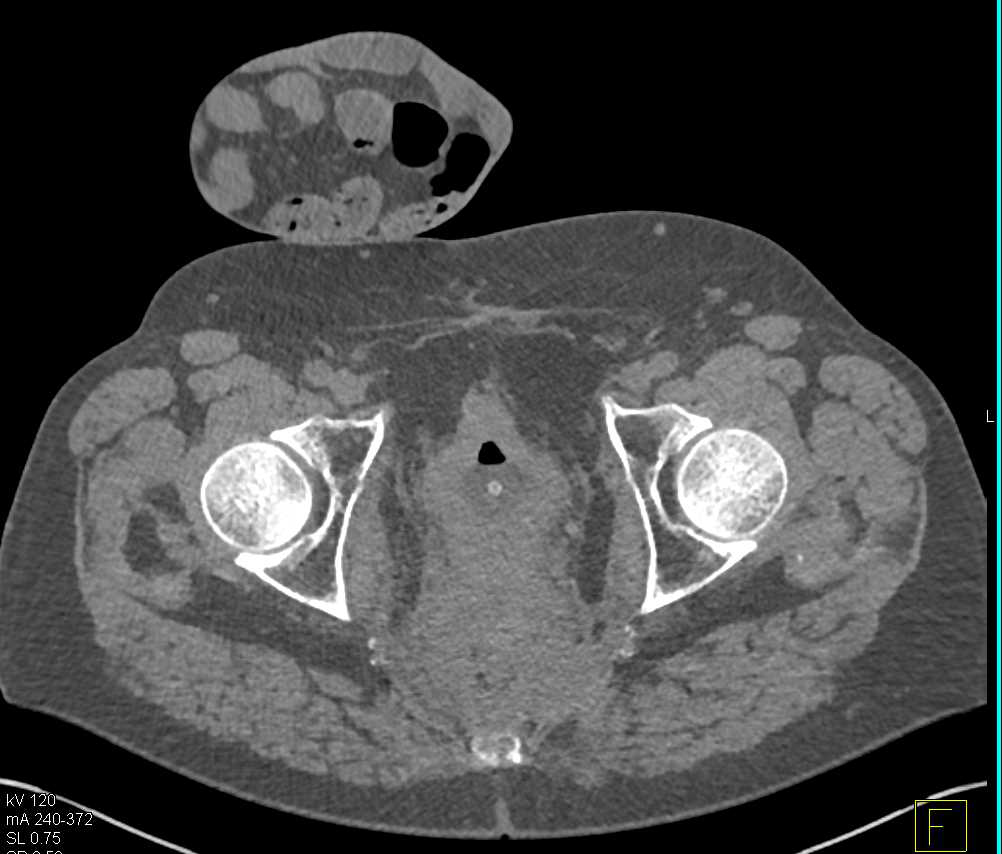

Subtle Transitional Cell Carcinoma Right Ureter